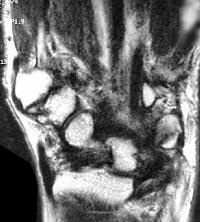

Sections through the carpal tunnel -  looking for a hook of hamate fracture or tendon discontinuity - were read as normal, although there may be a subtle signal irregularity through the hook of the hamate:

Is that a tendon rupture adjacent to the pisotriquetral joint?

The diagnosis was flexor tendon rupture, site uncertain. He was explored and found to have ruptured both flexors of the small finger within the carpal tunnel: